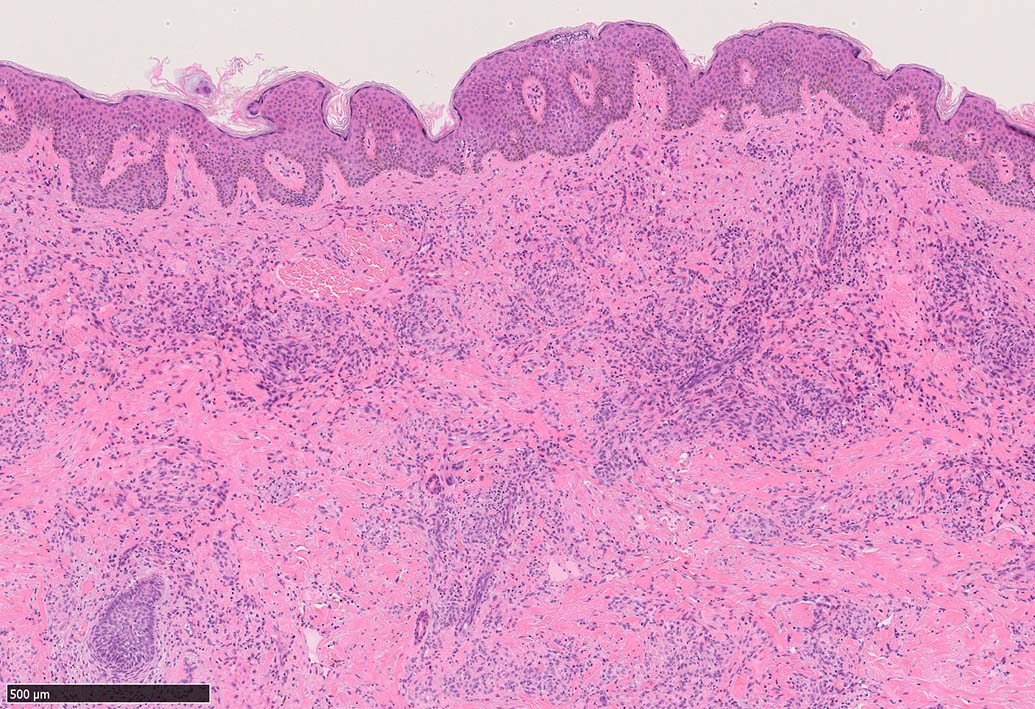

局面状病変の病理

病変は真皮から皮下脂肪織に及ぶようになり, 血管内皮様細胞による新生管腔の増加と拡張, 浮腫が著明になる. 赤血球漏出やヘモジデリン貪食細胞もめだつようになる.

膠原線維間に紡錘形細胞が増生してくる.

結節性病変の形成

紡錘形細胞が著しく増生し束状に走行する部分と, 内皮細胞様細胞による多数の小管腔構造が巣状にひろがり, 一見, 線維腫と血管腫が混在しているように見える. 一部の症例を除き, これらの増生細胞は異型性に乏しいことが多い.

細血管周囲に血管内皮様の紡錘形細胞が増生, 一部に赤血球をいれた裂隙の形成がある. 細胞の異型はみられず, mitosisの増多もない. hemosiderin-laden macrophageが散在する.

病変は真皮内に現局している. 初期斑状病変に相当すると考えられる. 本例では, 特徴とされる形質細胞浸潤増加はみられない.